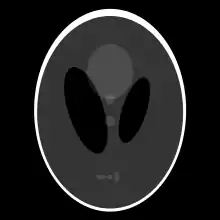

If a function represents an unknown density, then the Radon transform represents the projection data obtained as the output of a tomographic scan. Hence the inverse of the Radon transform can be used to reconstruct the original density from the projection data, and thus it forms the mathematical underpinning for tomographic reconstruction, also known as iterative reconstruction.

The process of reconstruction produces the image (or function in the previous section) from its projection data. Reconstruction is an inverse problem.

Thus in an image processing context the original image can be recovered from the 'sinogram' data by applying a ramp filter (in the variable) and then back-projecting. As the filtering step can be performed efficiently (for example using digital signal processing techniques) and the back projection step is simply an accumulation of values in the pixels of the image, this results in a highly efficient, and hence widely used, algorithm. Explicitly, the inversion formula obtained by the latter method is:[4]